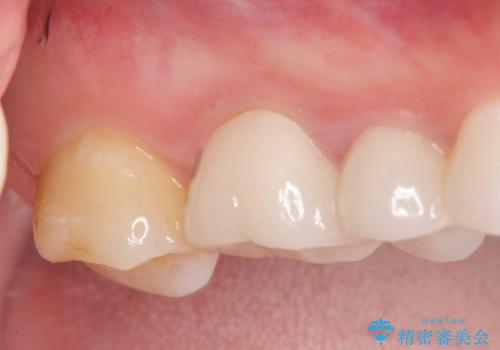

伸びてしまった奥歯、咬合平面を揃えたインプラント治療

- 右下の歯を虫歯で抜去し、インプラント治療を希望され来院されました。

インプラントを埋入するのに十分な骨は存在しますが、放置した間に上の歯が伸びてきてしまいクラウンのスペース不足な状態です。

通常このような場合、神経を除去し歯を短くしたのちインプラント治療を行いますが、今回はマイクロインプラントを用いて歯を歯ぐきの方向へ沈めたのち神経を温存する形でインプラント補綴を行いました。

伸びてしまった上の奥歯を、神経もとらず、クラウンにもせず治療することができ、喜んでいただくことができました。